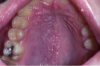

Kaposi's Sarcoma (Figure 1). People with AIDS-associated Kaposi's sarcoma (KS) frequently have oral lesions that visually manifest as red, brown, or purple patches or swellings. The palate is the most common site but lesions also occur on the gingiva, tongue, and oropharynx. KS is usually asymptomatic, but occasionally becomes painful because of ulceration or infection. Bulky gingival lesions that show when the patient smiles or talks may be of concern for cosmetic reasons and may also interfere with oral hygiene. Good oral hygiene and professional prophylaxis is, therefore, important in the management of oral KS. Small, well-localized lesions on the palate or gingiva are usually good candidates for treatment with intralesional injection of vinblastine (a drug used in combination with chemotherapeutics to treat cancers). Surgical removal and the carbon dioxide laser are also sometimes useful in removing such lesions. Small lesions may be treated on several occasions to achieve the best results. Large lesions may respond better to radiation therapy, either in a one-dose treatment or fractionated treatments delivered for ten to twelve days. Some patients experience episodes of mucositis during chemotherapy and xerostomia is sometimes a problem, but usually improve after therapy. Systemic chemotherapy is indicated for widespread or disseminated disease.

Figure 1. Kaposi’s sarcoma, oral lesions (courtesy of dentalcare.com)

Figure 1